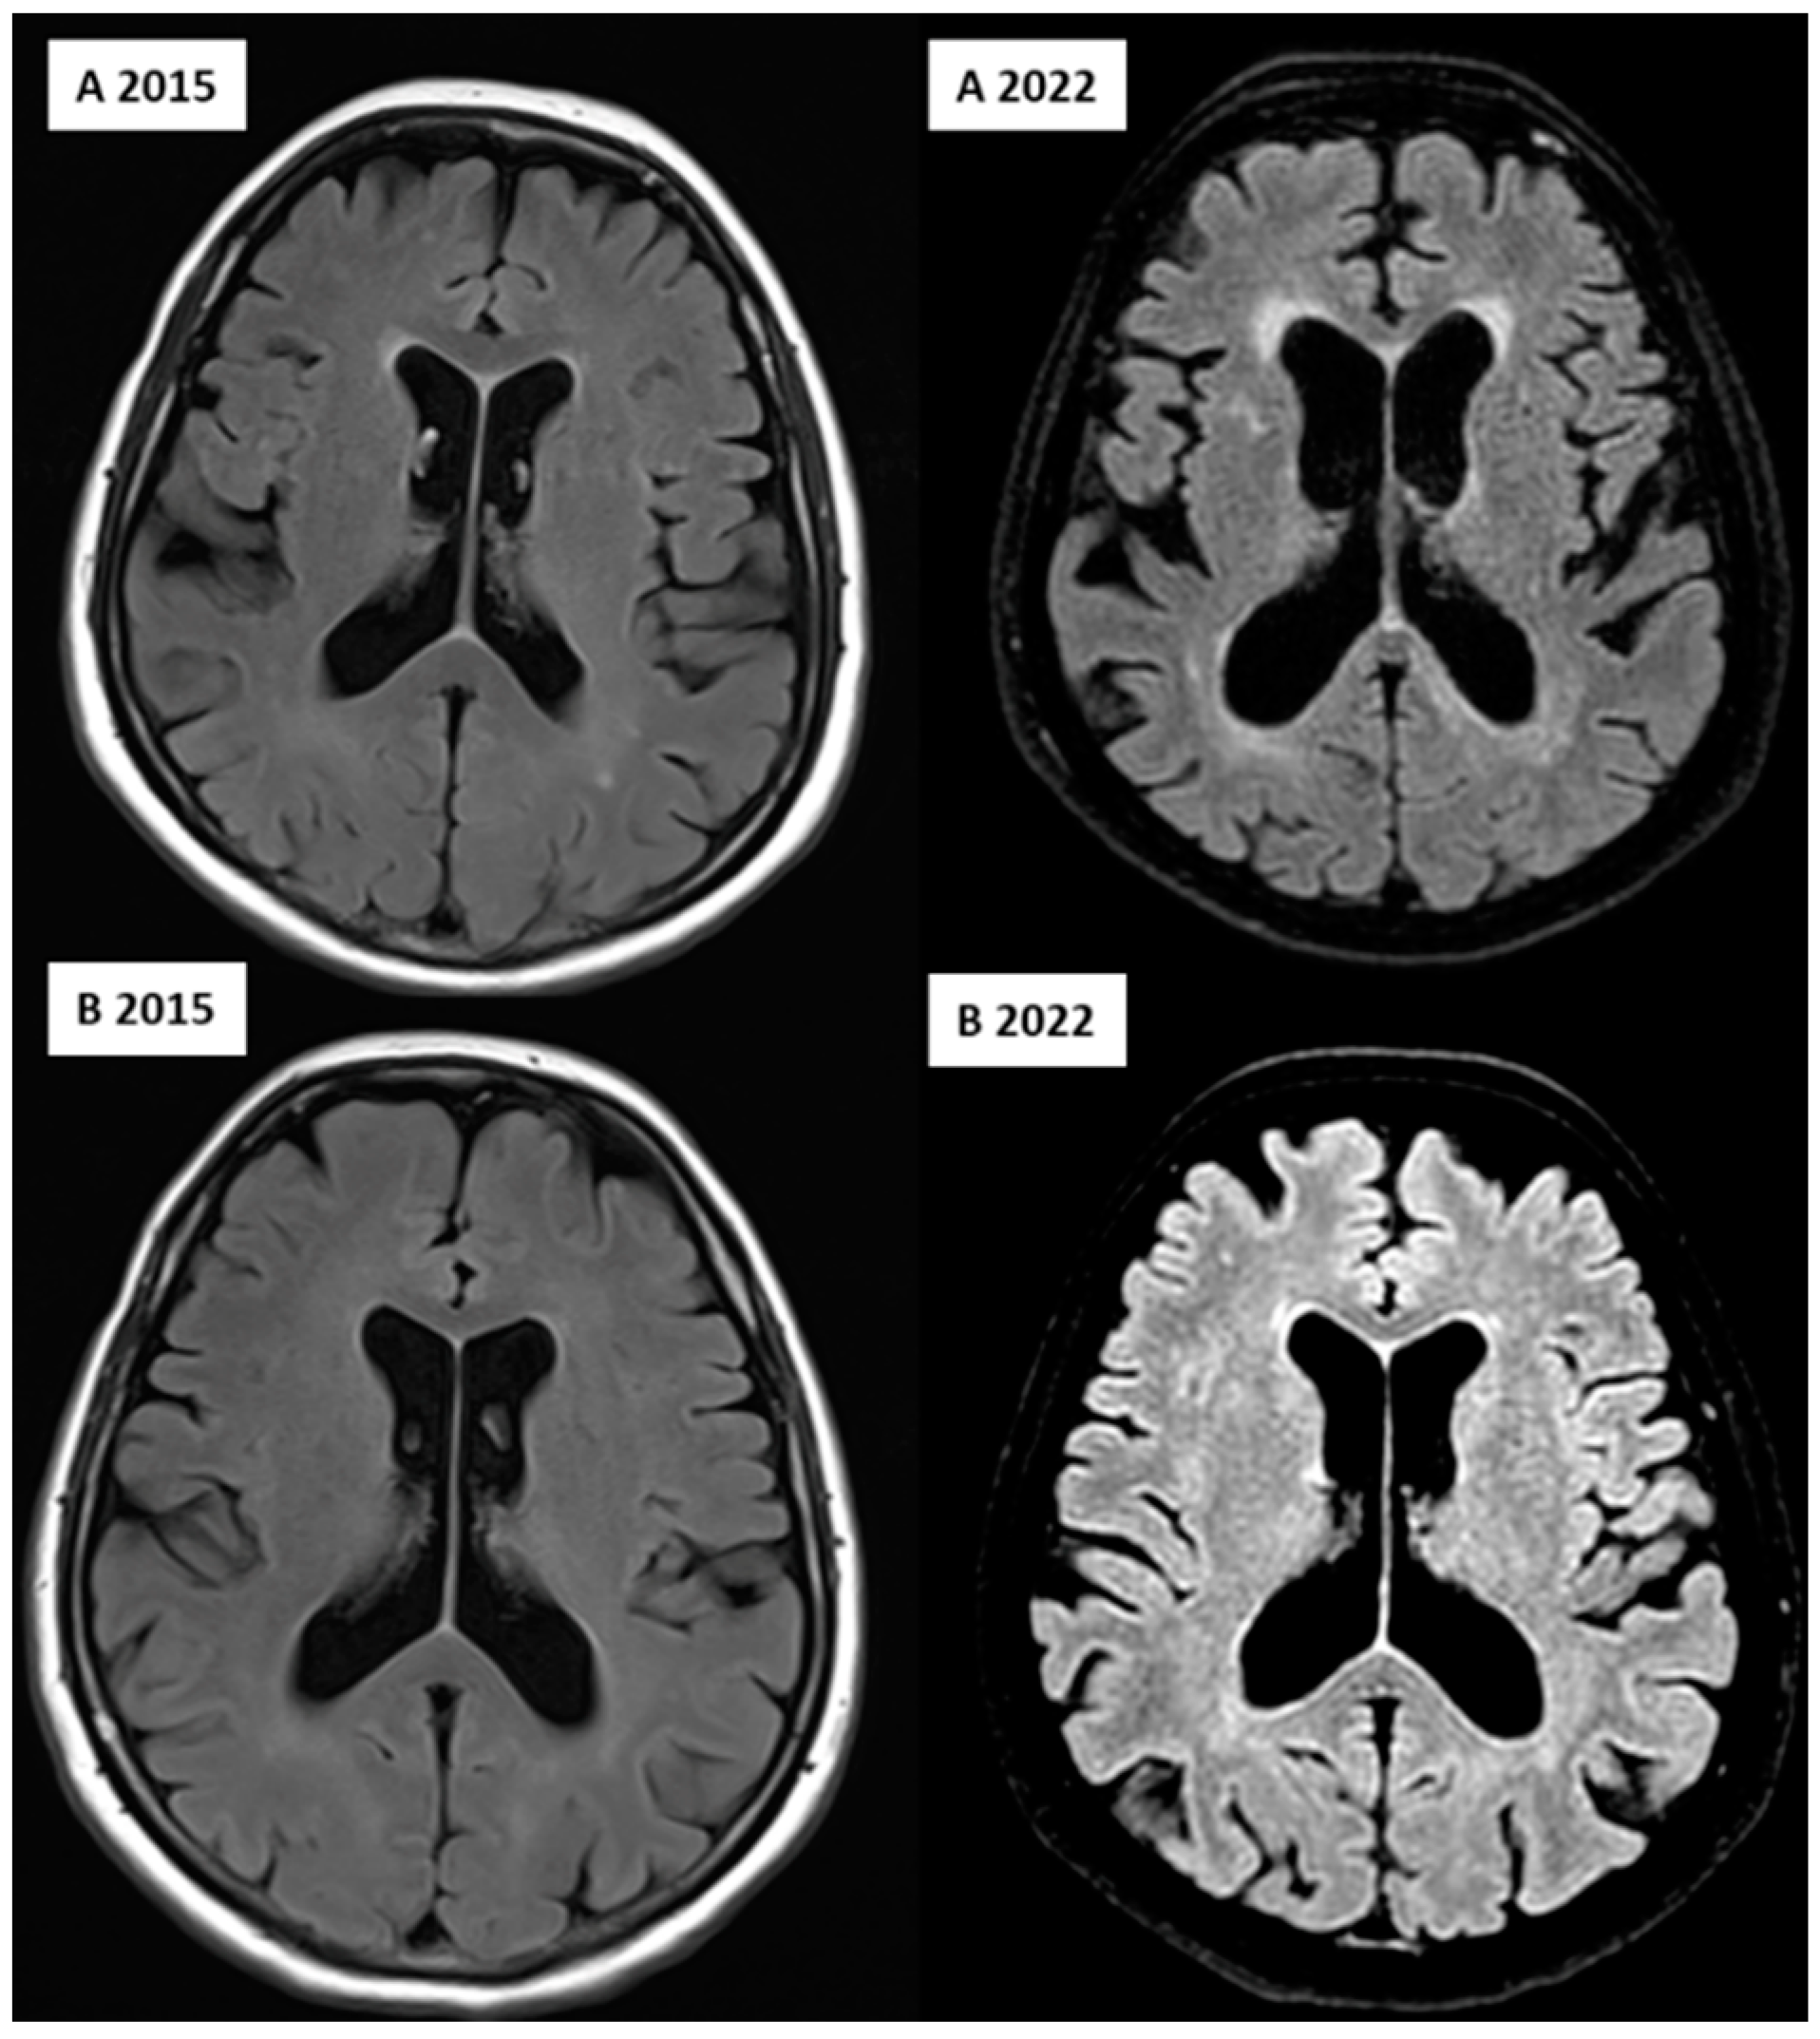

Figure 2.

FLAIR image of the affected (A, upper row) and unaffected (B, lower row) twin over 7 years, showing the progression of the WMHs in the deep and periventricular regions and ventricular dilation, indicating global cerebral atrophy; image from the Semmelweis University Medical Imaging Centre.

Concerning neuroimaging, we detected a left cerebellar lacunar stroke and signs of PSP (midbrain atrophy) in the affected twin; signs of normal-pressure hydrocephalus (NPH) were also observed. However, the latest brain MRI certified questionable signs of a possible beginner PSP, a narrow oedematous signal disorder in the cerebellar tonsils, and possible signs of normal-pressure hydrocephalus in the unaffected twin (Figure 1 and Figure 2).

Many studies have reported various structural neuroimaging findings in T1- weighted, T2-weighted, and FLAIR images, including midbrain atrophy, atrophy of the superior cerebellar peduncle, and frontal and parietal cortical atrophy, which were present in the affected twin. Moreover, dilatation of the third and fourth ventricles and the aqueduct of Sylvius was also observed, which was present in the twin pair, with dominance in the affected twin. In addition, atrophy of the subthalamic nucleus is the most typical trait of PSP. The most characteristic pathological finding is the atrophy of the midbrain, which is demonstrated by the hummingbird sign as a result of rostral midbrain atrophy observed on mid-sagittal images, which was observed in the affected twin [6,36]. Interestingly, MRI signs of possible beginner PSP were suspected in the MRI imaging for the unaffected twin despite them being clinically asymptomatic, including narrow edematous signal disorder in the cerebellar tonsils and possible signs of NPH. The WMH analysis demonstrated remarkable differences between the twins, especially in the total, periventricular, and juxtacortical WMH lesion volume, which were higher in the PSP-affected twin. In addition, a remarkable decrease in brain volumes, mainly in total gray matter and frontal lobe volume except for temporal lobe volume, was observed. In the affected twin, a left cerebellar lacunar stroke was also observed, which referred to a vascular (possibly atherosclerotic) origin.